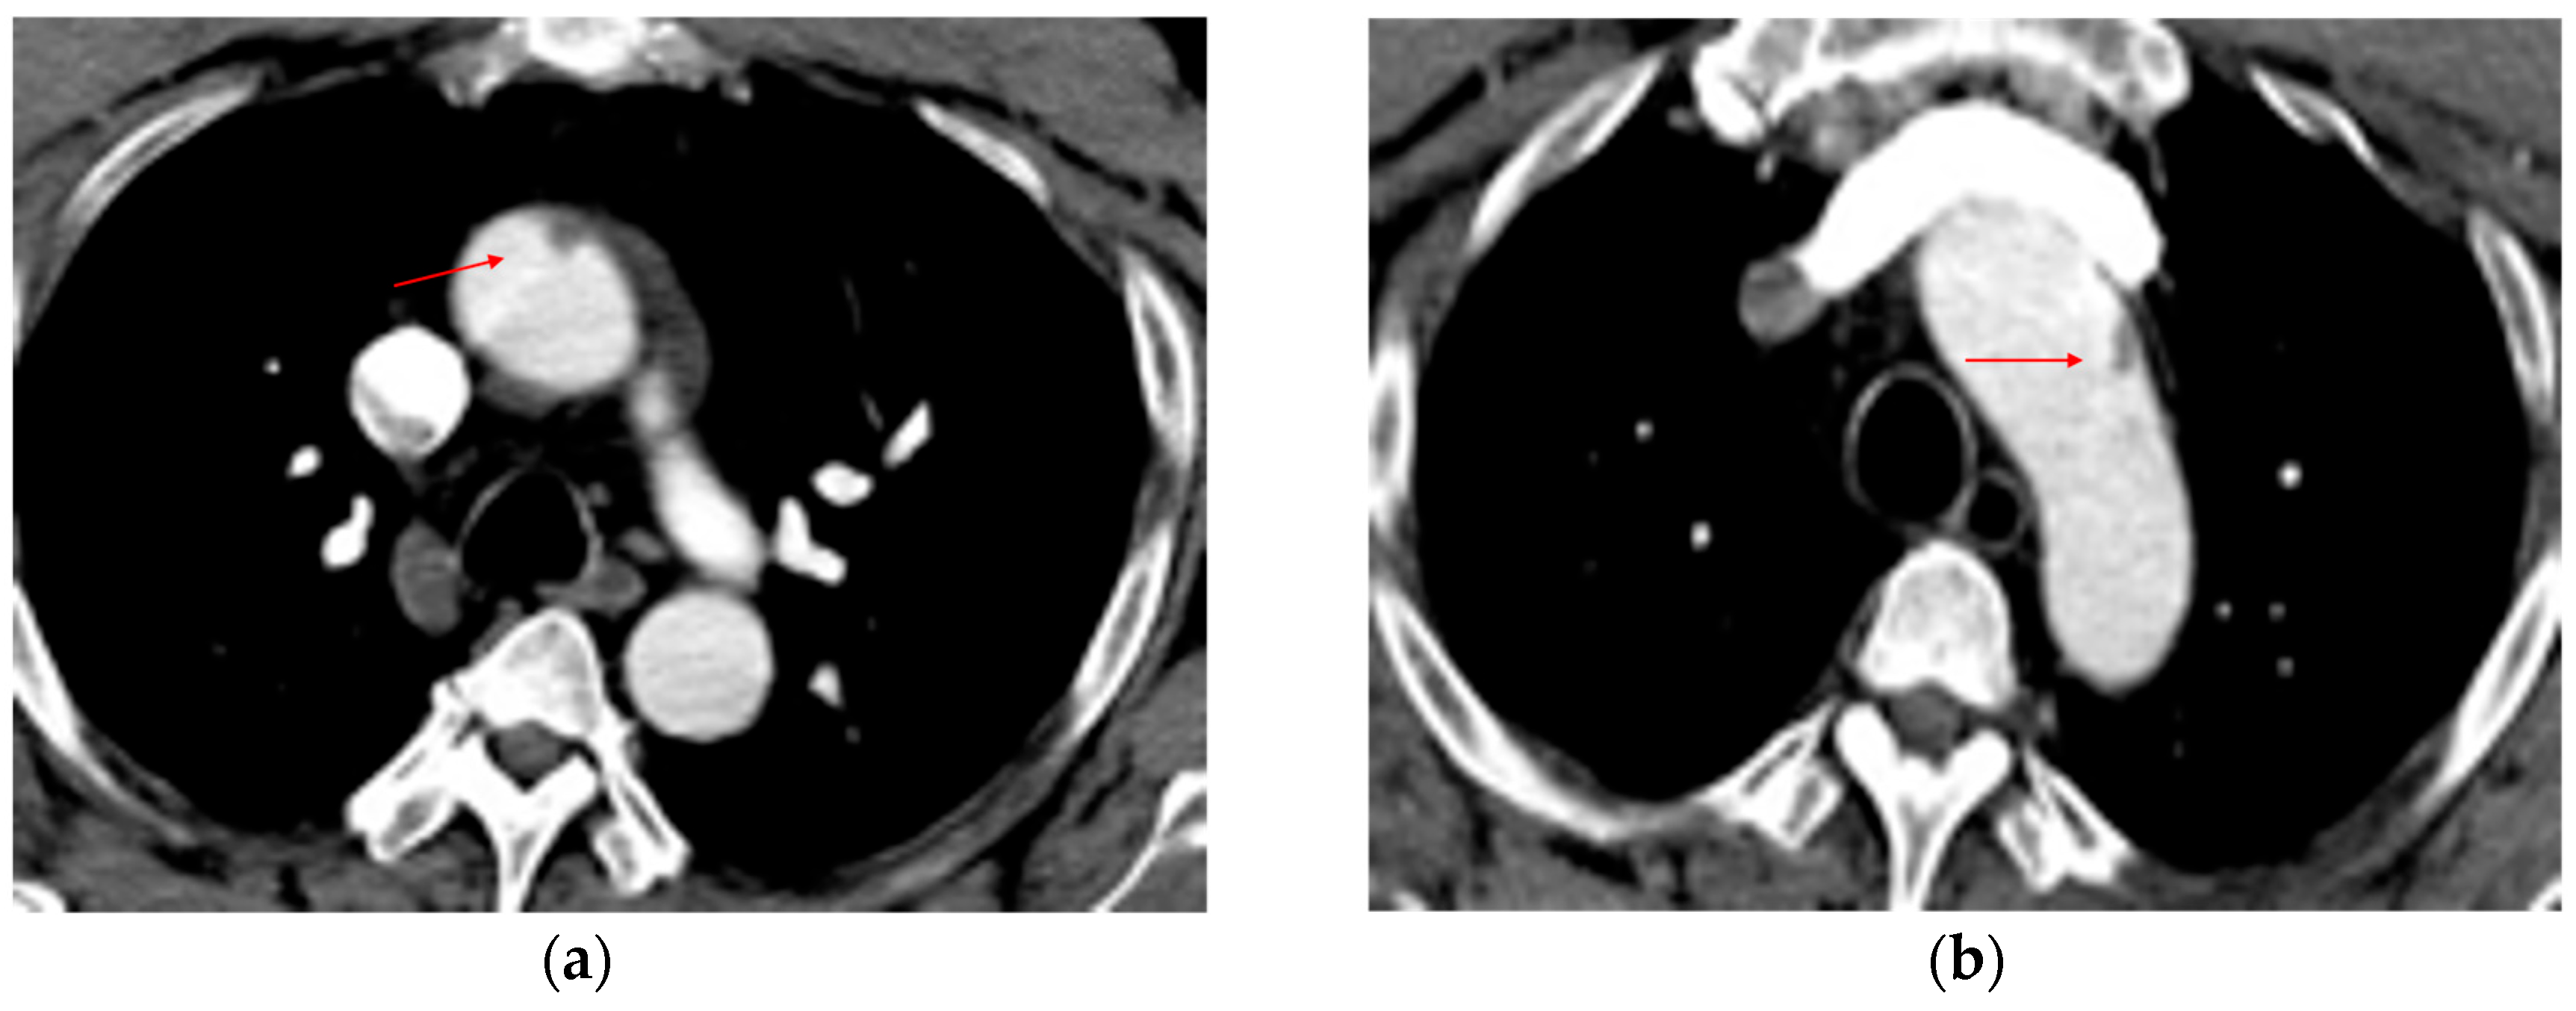

7.2. Complications Following Endovascular Repair

7.3. Complications Following Open Surgical Repair